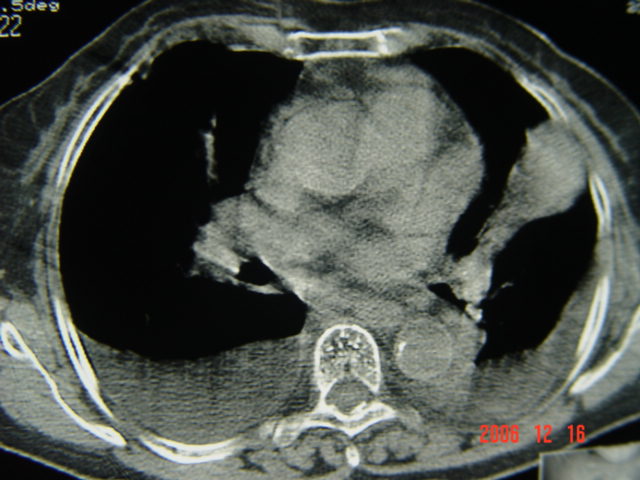

左第八肋腋侧呈膨胀性骨质破坏,内侧见软组织密度肿块。左肺舌段呈楔形实变,基底近胸壁,尖端向肺门。双侧胸壁后缘见新月形水样密度区。

考虑:1、左第8肋骨转移瘤;

2、左肺舌叶肺栓塞可能性大;

3、双侧中量胸腔积液。

不要考虑的过于复杂,就是个肺癌,肋骨转移,隆突下淋巴结肿大,双胸腔积液

左肺舌段片团影考虑肺癌可能性大

左下肺部分肺不张

左第8肋骨转移瘤